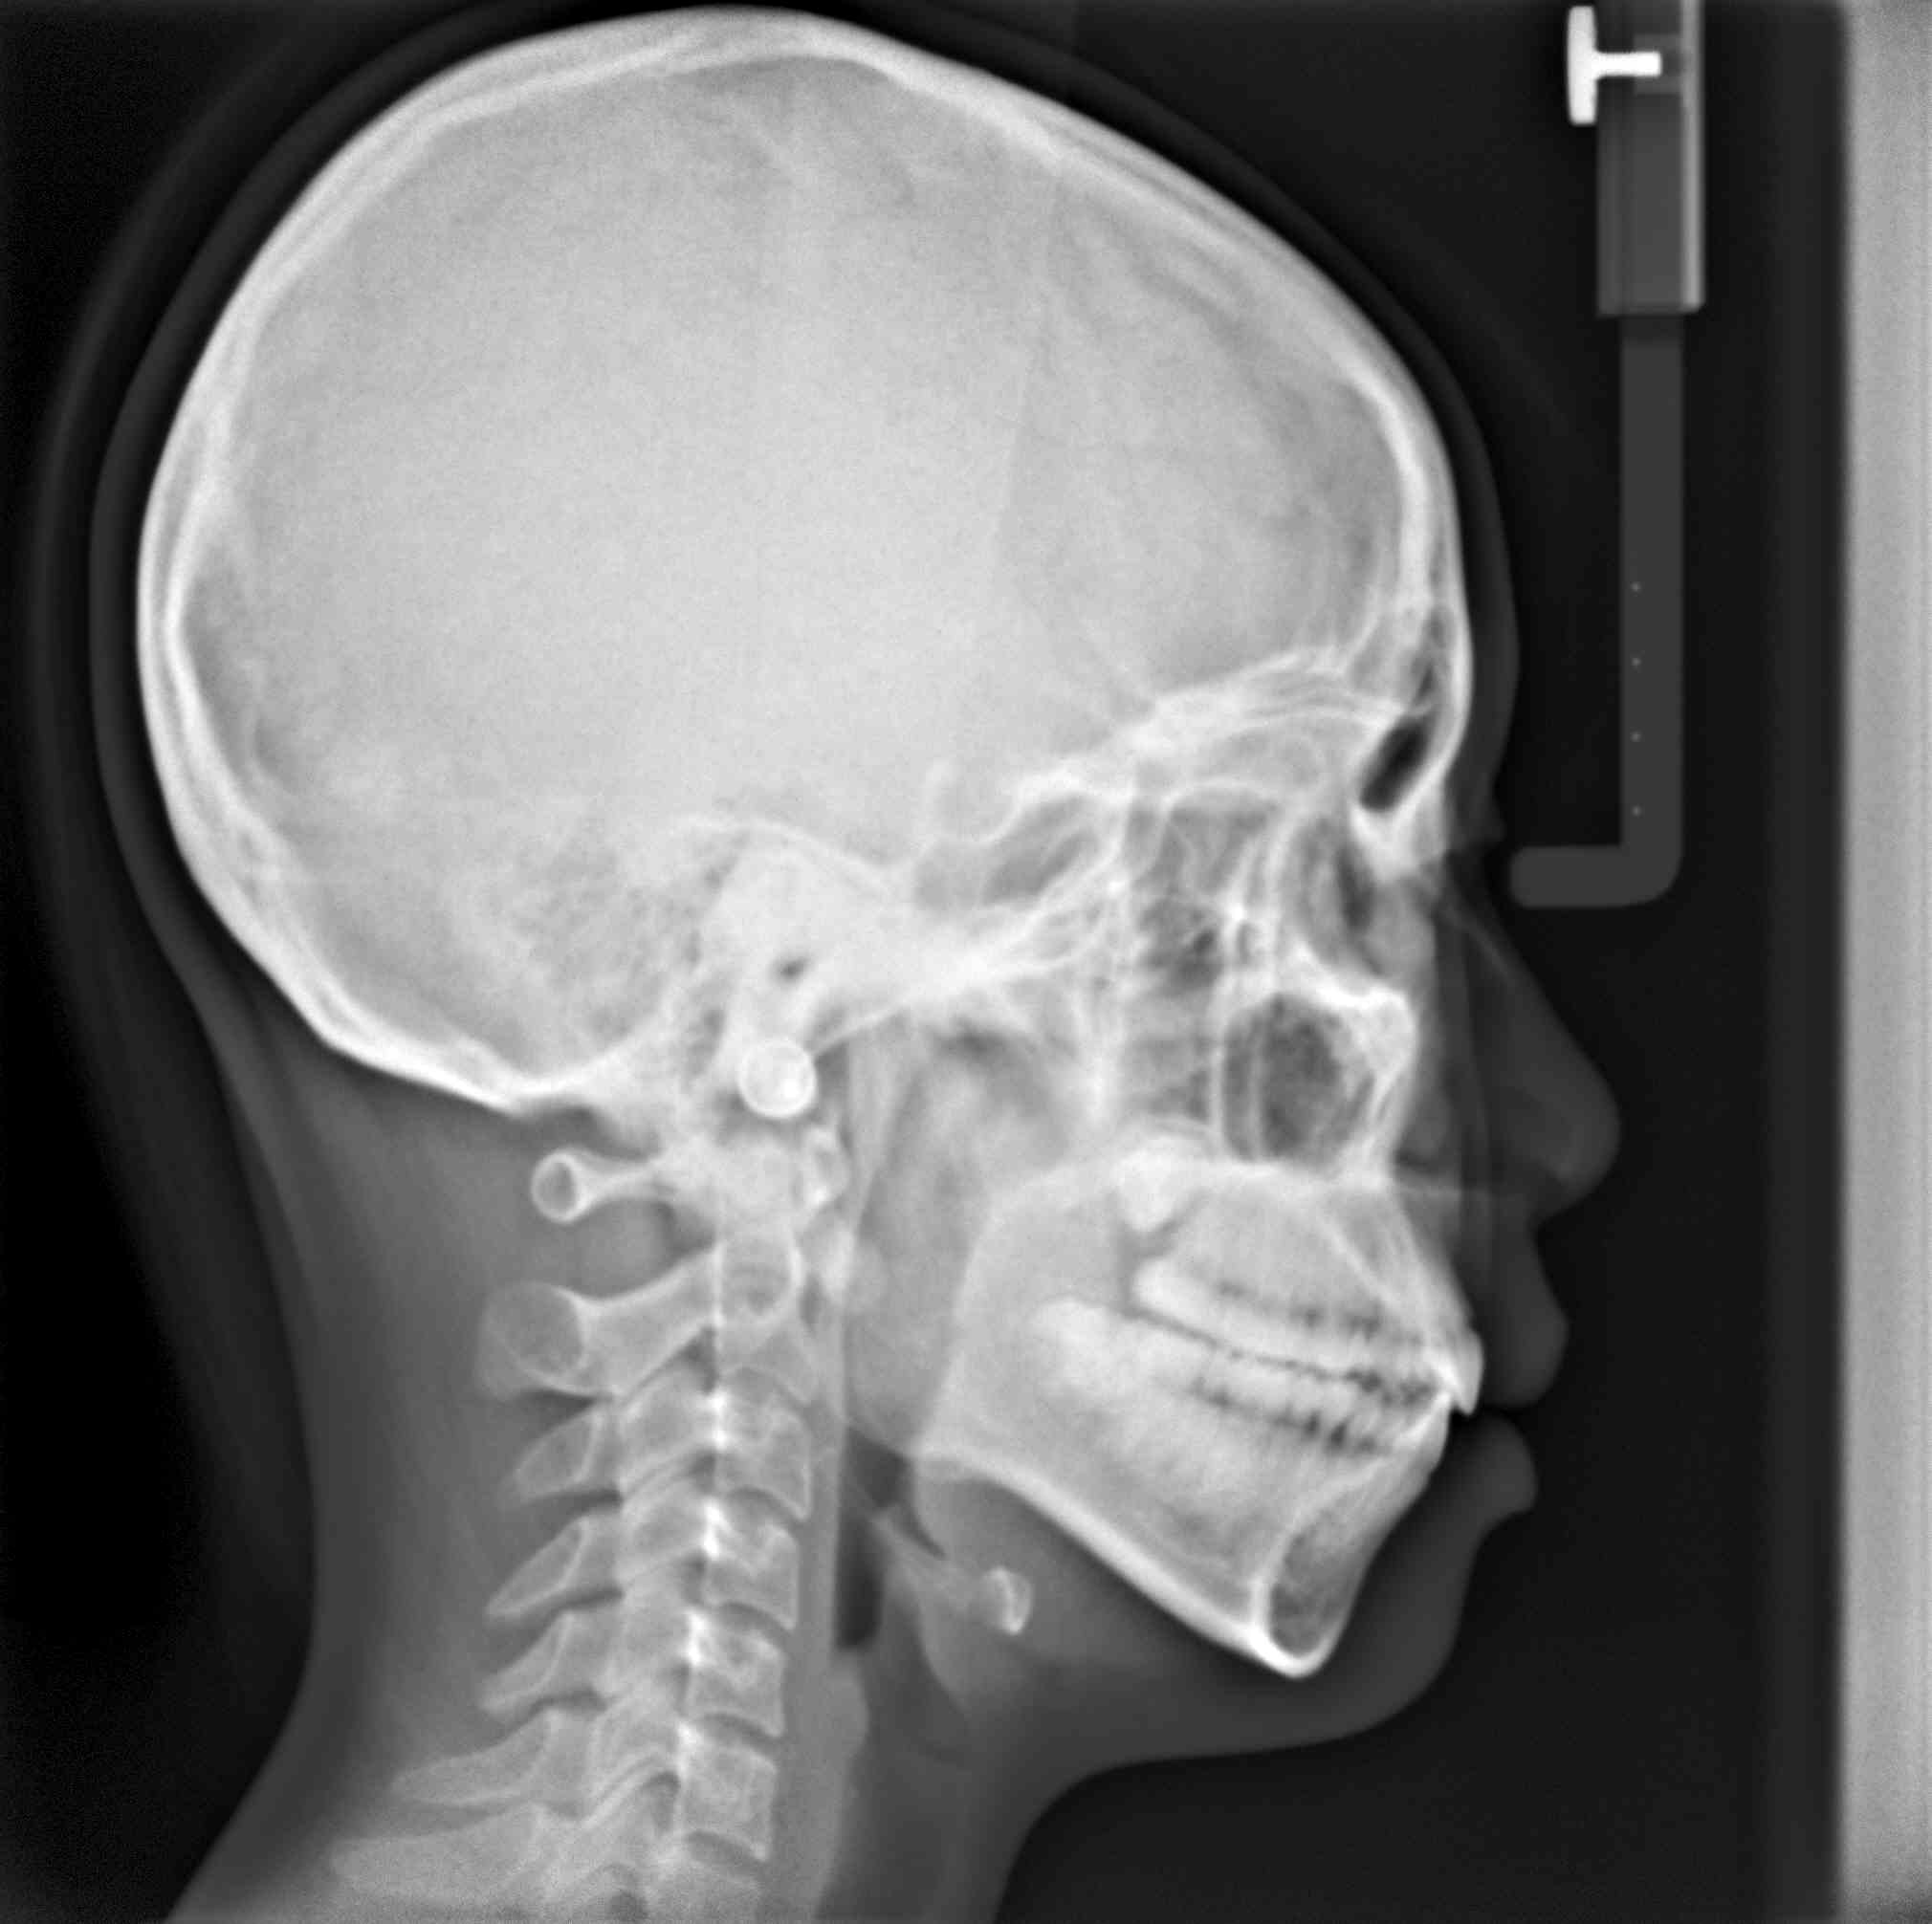

拔牙案例 首頁 案例分享 齒顎矯正 拔牙案例 - 拔牙案例 - 年紀:15歲 矯正方式:隱適美隱形矯正 時間:30個月 主訴:暴牙、笑起來不好看、咬合不正 矯正前 矯正後 矯正前 矯正後 矯正前 矯正後 聲明:本所療程皆由專業醫生評估後,依照個人口腔狀況進行治療。因每位患者個別狀況不同,術後狀況也不盡相同,需親來本所由醫生評估。